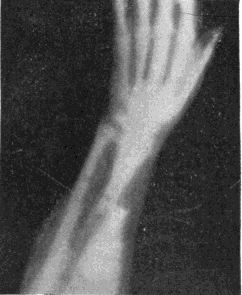

118. X-rays Begin before Striæ End. Edison and Thomson, E.

207. A Colles’ Fracture Detected by X-rays. Morton